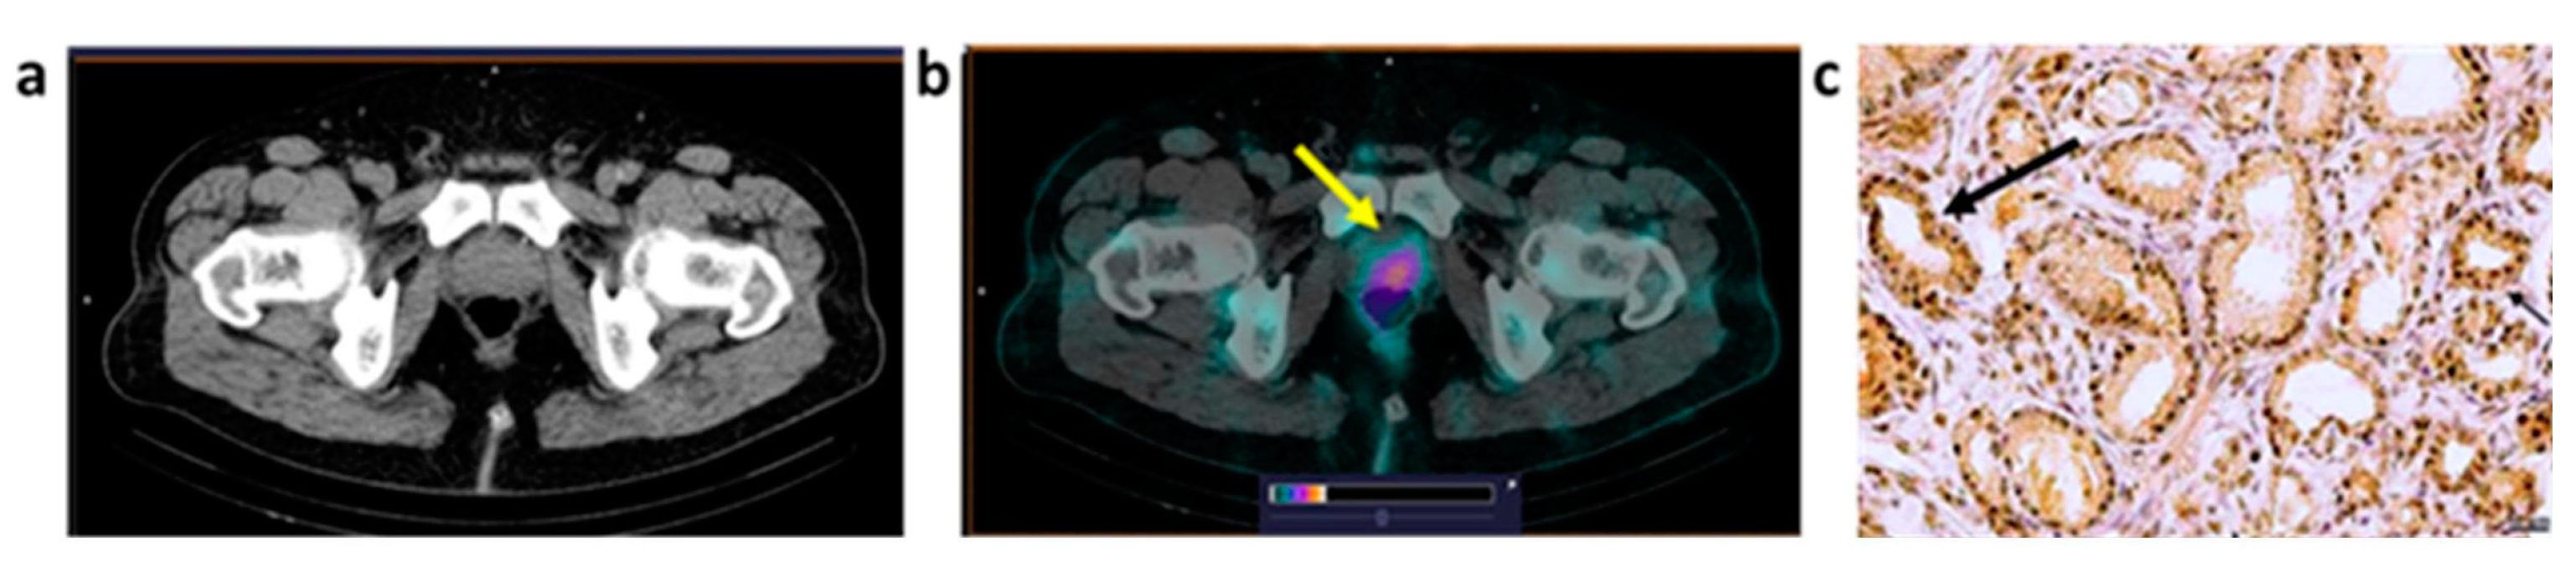

| P1 | 68 | PAA G2 GS 7 (3+4) PSA = 11.4 | T2N0M0 | 1.67 (1.6 × 2.5) | 7.3 | 2+ |

| P4 | 65 | PAA G1 GS 6 (3+3) PSA = 9.25 | T1bN0M0 | 1.14 (1.8 × 2.0) | 4.2 | 1+ |

| P5 | 66 | PAA G1 GS 6 (3+3) PSA = 11 | T2N0M0 | No accumulation | 3+ | |

| P6 | 70 | PAA G2 GS 7 (4+3) PSA = 7.93 | T2aN0M0 | No accumulation | 0 | |

| B1 | 34 | IC NST G2 | T2N0M0 | T: 1.41 (2.8 × 2.2) | 2.2 | T: 3+ | T2N0M0 |

| B2 | 41 | IC NST G2 | T2N2M0 | T: 1.75 (3.8 × 2.2) LNM: 1.8 (1.3) | T: 35 LNM: 16.3 | T: 1+ LNM: 2+ | T2N3M0 |

| B3 | 40 | IC NST G2 | T2N0M0 | T: 0.87 (5.1 × 2.2) LNM: 1.8 (1.4) | T: 10.8 LNM: 7.1 | T: 0 LNM:1+ | T3N3M0 |

| B4 | 69 | ILC G1 | T2N0M0 | T: 0.57 (6.8 × 3.2) LNM: 0.58 (2.5) | T: 7.8 LNM: 6 | T: 1+ LNM: 1+ | T2N1M0 |

| B5 | 56 | IC NST G2 | T2N1M0 | T: 0.87 (4.0 × 1.7) LNM: 1.8 (2.3) | T: 14.5 LNM: 11.3 | T: 0 LNM: 0 | T2N1M0 |

| B6 | 50 | IC NST G1 | T1N0M0 | T: 0.43 (1.5 × 1.5) | T: 4.3 | T: 3+ | T1N0M0 |

| B7 | 62 | IC NST G2 | T1N0M0 | T: 0.50 (1.5 × 1.4) | T: 2.7 | T: 1+ | T1N0M0 |